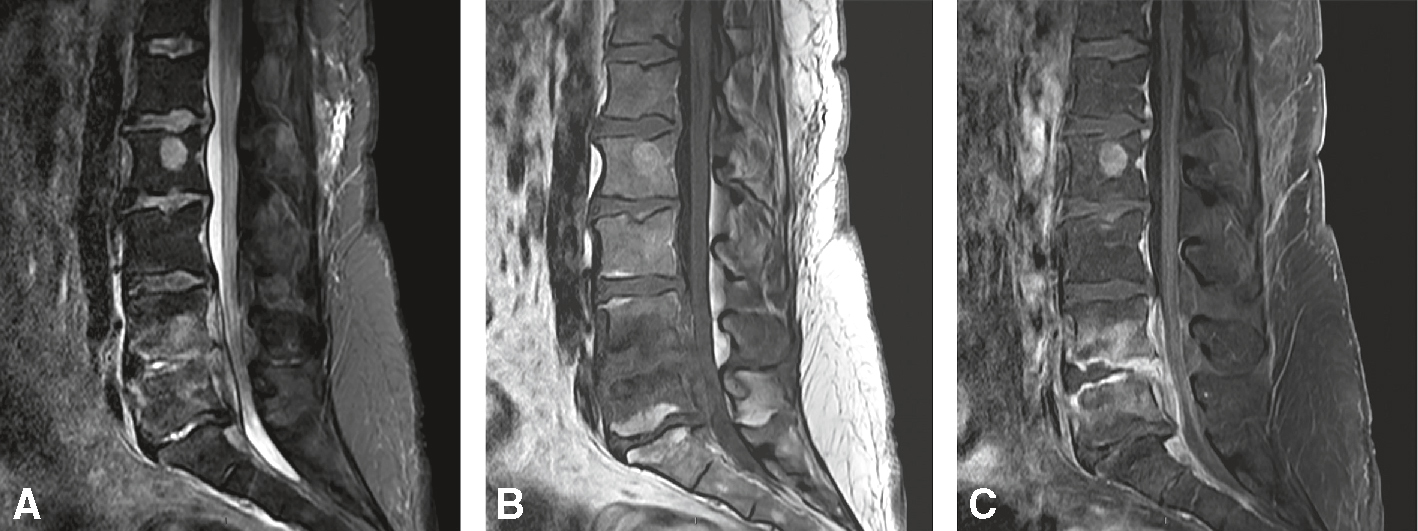

4 93Spondylodiscites et épidurites infectieuses

À l’origine d’une compression médullaire extradurale (si bacille de Koch, il s’agit du mal de Pott) (fig. 7.6).

Compression de la queue de cheval liée à une spondylodiscite infectieuse (ici à staphylocoques). Hyposignal T1/hypersignal T2 des plateaux vertébraux en L4 et L5, en miroir, prenant le contraste après injection, avec spondylodiscite du disque et collection centimétrique intradiscale, atteignant l’espace épidural antérieur (épidurite comprimant la queue de cheval en regard). Intégrité des autres corps vertébraux (angiome vertébral bénin en L2). A. Sagittal T2.

et C. Sagittal T1 sans puis avec injection de gadolinium FAT-SAT.Cette série d’IRM sagittales lombaires en pondérations T1, T2 et STIR (A, B, C) met en évidence une spondylodiscite infectieuse, probablement à staphylocoques. Sur l’image A, en séquence STIR, un hypersignal diffus est visible au niveau du disque intervertébral et des plateaux vertébraux adjacents, avec un œdème inflammatoire marqué. L’image B en T1 montre une perte du signal du disque et des corps vertébraux adjacents, traduisant une destruction osseuse et discale. Sur l’image C en T2, on observe une protrusion du matériel infecté dans le canal rachidien, entraînant une compression visible des racines de la queue de cheval. L’ensemble est caractéristique d’une spondylodiscite évoluée avec atteinte neurologique.